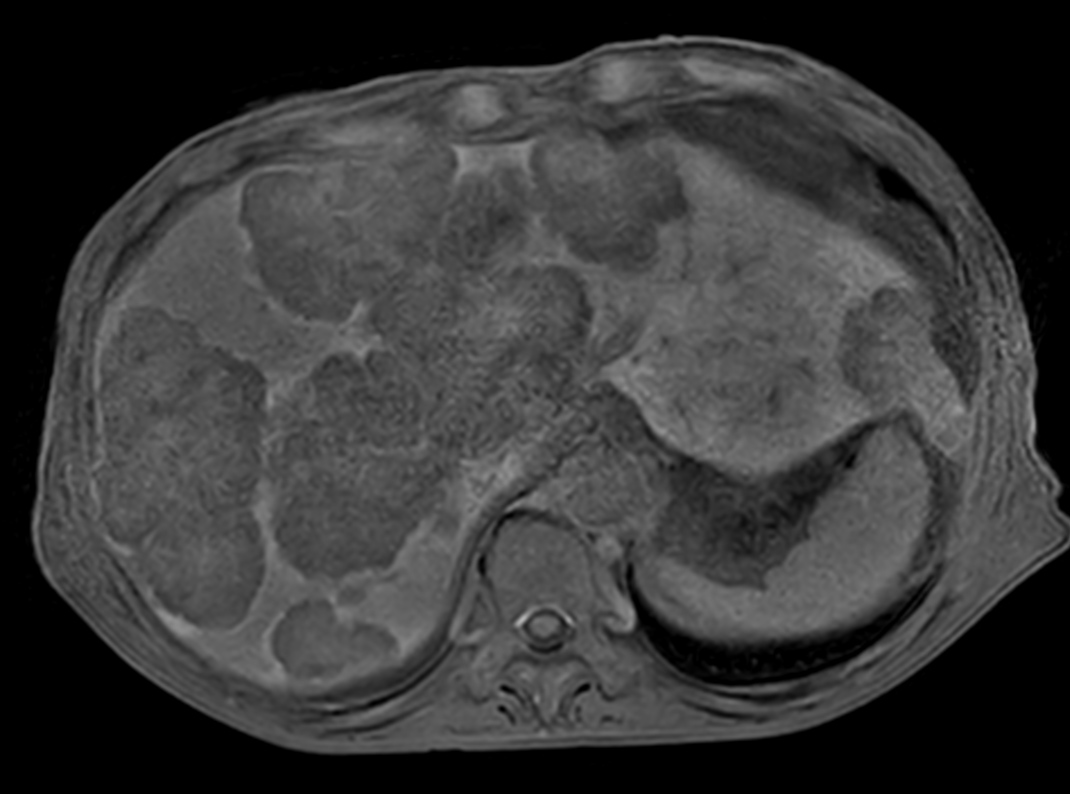

Patient with liver metastasis. The ExamCard includes techniques for efficient fat-free imaging over large field-of-views (mDIXON XD), a procedure for non-invasive liver fat quantification (mDIXON Quant), a multi-phase contrast-enhanced sequence (4D FreeBreathing) to improve imaging confidence and Compressed SENSE to accelerate the entire exam.

T1w mDIXON XD FFE Compressed SENSE